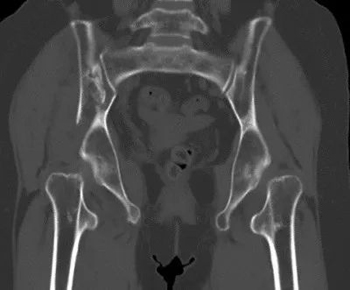

针对这名患者,创伤骨科机器人团队利用智能化骨折复位机器人对骨盆骨折三维CT影像做出智能化复位规划。

图丨机器人在术前做出智能复位规划